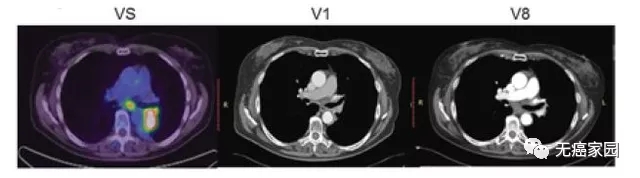

接下来,小编展示联合疗法中一个典型的成功案例,如图所示:治疗1~2个月后复查,肺部肿瘤完全消失,并且疗效已经保持了18个月。